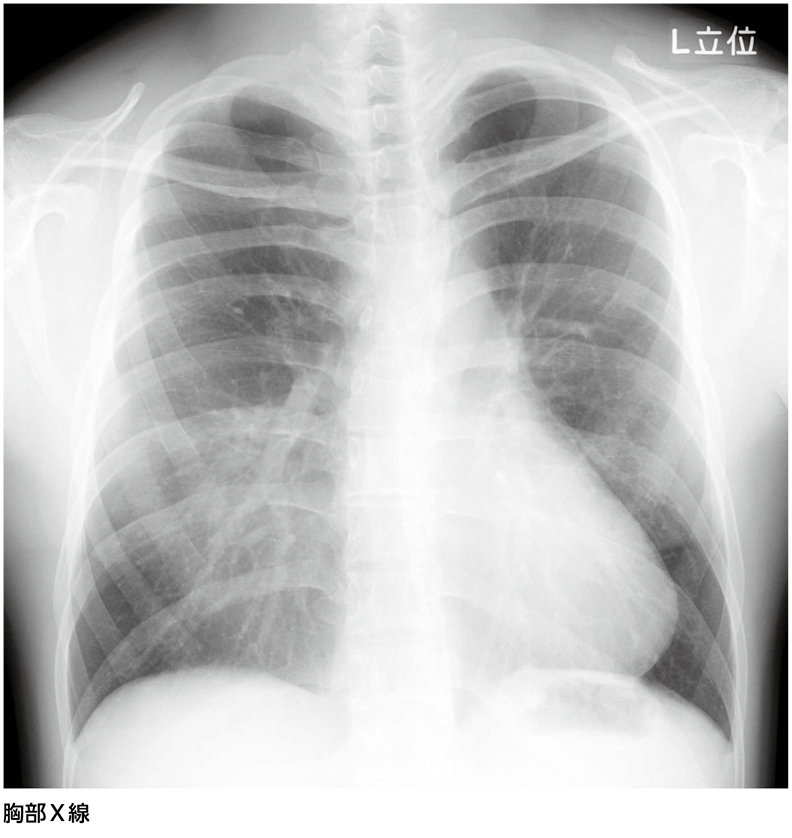

TOP > Web医事新報を読む > 肺炎? 中葉無気肺? ……診断は?[画像診断道場~実はこうだった(330)]

20歳代,男性。健康診断の胸部X線検査で胸部異常所見を指摘された。自覚症状はない。